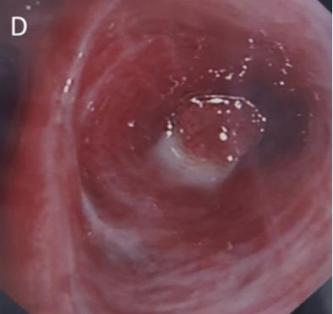

图2. 支气管镜影像CT检查怀疑恶性肿瘤

CT检查示右后上叶实变,没有看到含气支气管影,怀疑是支气管内肿瘤导致阻塞后实变(图1 A)。支气管内膜异常也出现在中间支气管和左主支气管(图1B、1C)。支气管镜检查显示,左侧主支气管、右侧中间支气管和右上叶后段支气管有大量息肉样肿块。(图2)